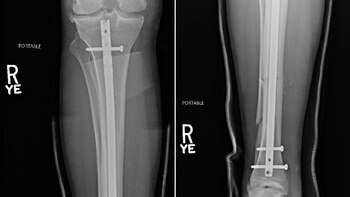

Weidman debió ser trasladado inmediatamente a un hospital. Día a día compartió su progreso tras la operación a la que fue sometido. Una de las imágenes más impactantes la dejó con las fotos de las radiografías que le tomaron, donde se ve tanto el grado de la lesión como los múltiples tornillos que debieron colocarle en sus huesos.

“Antes y después de las radiografías de esta pesadilla. La principal preocupación es el hueso perforado a través de la pantorrilla y la piel cuando pongo mi peso sobre él, asegurándome de que la laceración no se infecte”, relató en sus redes sociales tras compartir las fotos de las radiografías.

“Me pusieron una varilla de titanio a través de la tibia para que pasaran por la rodilla y la pusieran y la perforaran a través de la tibia para enderezarla y endurecerla. Mi peroné también se rompió”, agregó más detalles en diálogo con TMZ, donde aclaró que pasarán al menos de 6 a 12 meses para que pueda volver a entrenarse.